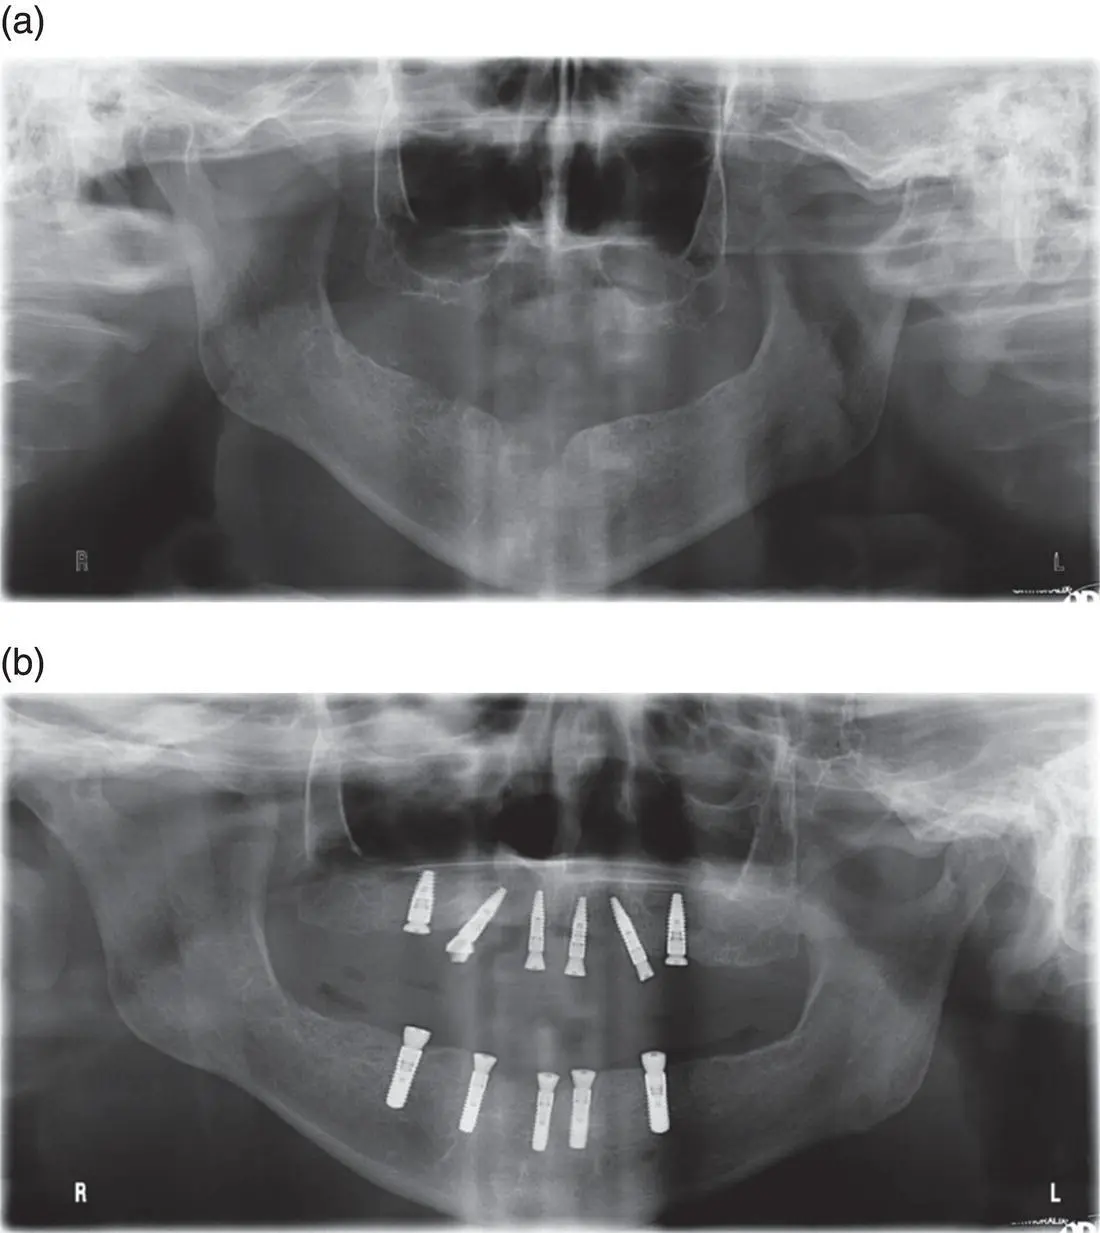

Figure 7.4 Implant placement following maxillary sinus augmentation in a staged approach. Sinus floor elevation (SFE) via a lateral window approach was performed on both the right and left posterior edentulous segments, as the bone quality and residual bone height as shown in the panoramic radiograph (a) were not favourable for a simultaneous implant placement in conjunction with the grafting procedure. Following sinus graft consolidation over a period of six months, implants were placed in the posterior segments uneventfully as shown in the panoramic radiograph (b).